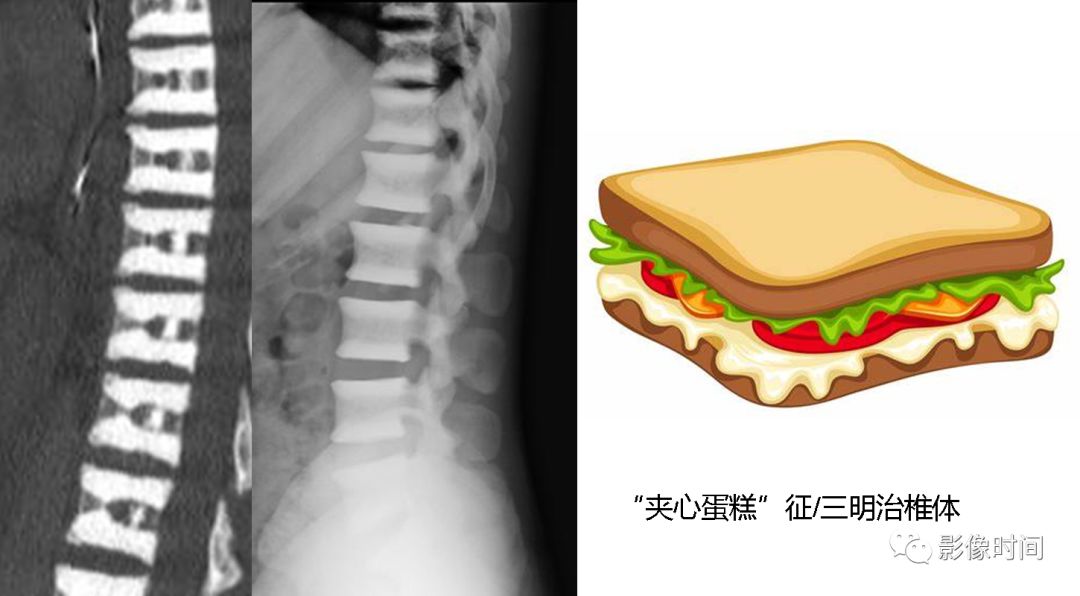

26夹心蛋糕征与橄榄球衫椎

前言:夹心蛋糕及橄榄球衫椎均用于描述椎体,上下终板区域带状密度增高,而中心区域密度相对低,高低密度区间杂。部分同道可能会混用,但两者有所不同,查询国内外书籍、文献及网页,总结如下:中文书籍中的所谓「夹心蛋糕征」,主要用于描述石骨症(也称骨硬化症),与英文「Sandwich vertebral body」(三明治椎体)对应,而橄榄球衫椎(Rugger-jersey spine)主要用于描述甲状旁腺功能亢进(原发及继发),国内主要用于描述肾性骨病,继发甲状旁腺功能亢进。

两者表现类似,区别在于三明治椎硬化带密度更高,边界更清晰,而橄榄球衫椎硬化带边界不够清楚,也没有那么致密(注:确实有混用情况,但大部分如上所说)。

典型病例

病例 1,石骨症。腰椎正侧位片示腰椎椎体上、下终板区域显著硬化,而中央区密度较低,呈夹心蛋糕征/三明治椎体。

病例 2,69 岁女性,肾性骨病。视野内诸骨密度不均匀增高,骨小梁模糊。腰椎椎体上下终板区域密度增高,中心区域密度较低,边界不清,呈「橄榄球衫椎」表现。